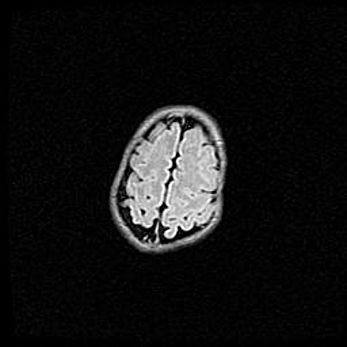

Лейкомаляция с кистозно-глиозной дегенерацией головного мозга.

Возраст: 2 месяца 25 дней

Вес: 6400 г

Окружность головы: 40 см

Срок гестации: 41 неделя

Лейкомаляцию относят к ишемически-гипоксическим повреждениям головного мозга, диагностируемым у новорожденных. При лейкомаляции в головном мозге обнаруживают очаги некроза, возникшие после тяжелой гипоксии и нарушения кровотока. В процессе морфогенеза очаги проходят три стадии: 1) развития некроза, 2) резорбции и 3) формирования глиозного рубца или кисты. Перивентрикулярная лейкомаляция (ПЛ) встречается примерно в 12% случаев среди новорожденных, обычно – у недоношенных детей, причем, частота ее зависит от массы, с которой младенец появился на свет. Наибольшее число малышей страдает лейкомаляцией, если масса при рождении 1500-2500 г.